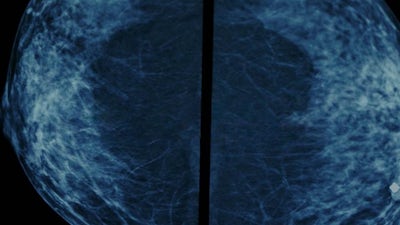

On Behalf of Our Breasts: The Dark Side of Screening

Breast cancer kills. But are blanket programs that screen all women, rather than those with symptoms, doing more harm than good? Controversially, studies into the effects of these programs show they do not reduce the risk of dying from breast cancer. Healthy women are receiving unnecessary diagnoses of pre-cancerous conditions that are unlikely to develop and many are harmed by unnecessary treatment. We follow four women from around the world who are facing the fear of cancer.